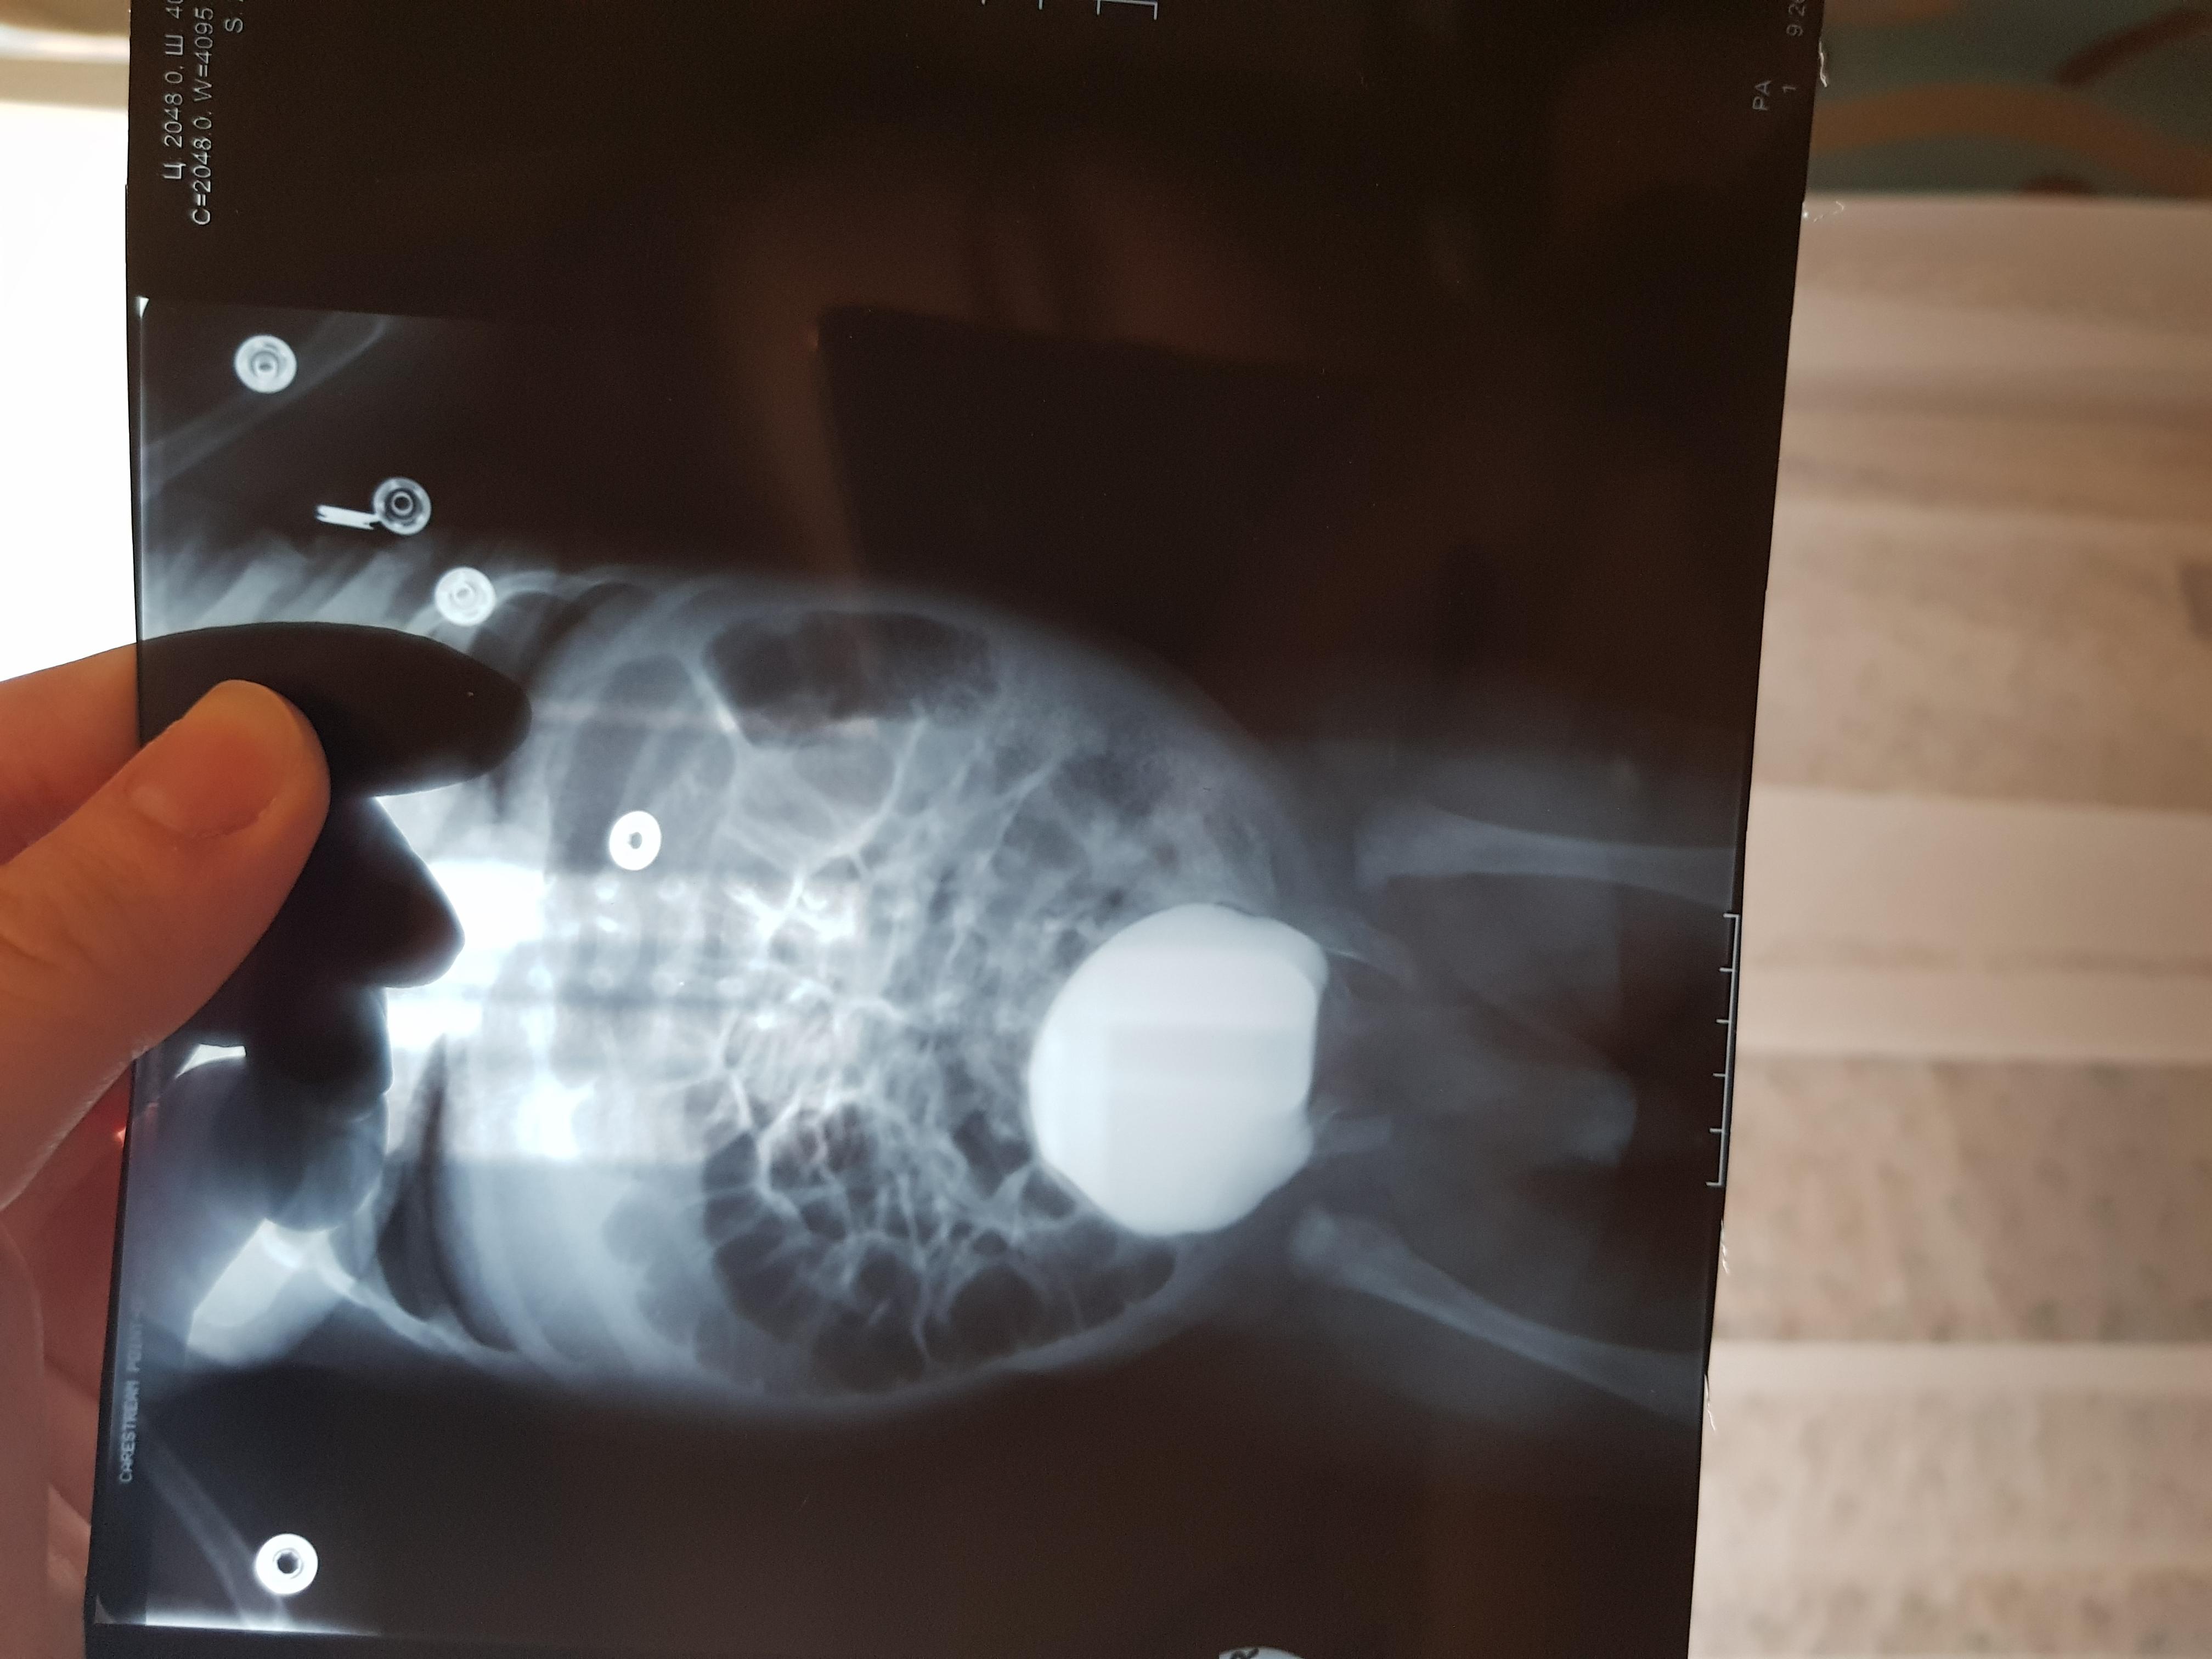

Болезнь Ормонда (ретроперитонеальный фиброз, забрюшинный фиброз) – хроническое воспаление жировой клетчатки забрюшинного пространства, которое постепенно приводит к компрессии и нарушению проходимости трубчатых структур данного анатомического участка. Чаще всего, в качестве этих тубулярных структур выступают мочеточники.

У меня есть сомнения, что причиной гидронефроза в Вашем случае явилось именно это состояние.

Возможно речь идет о пузырно-мочеточниковом рефлюксе.